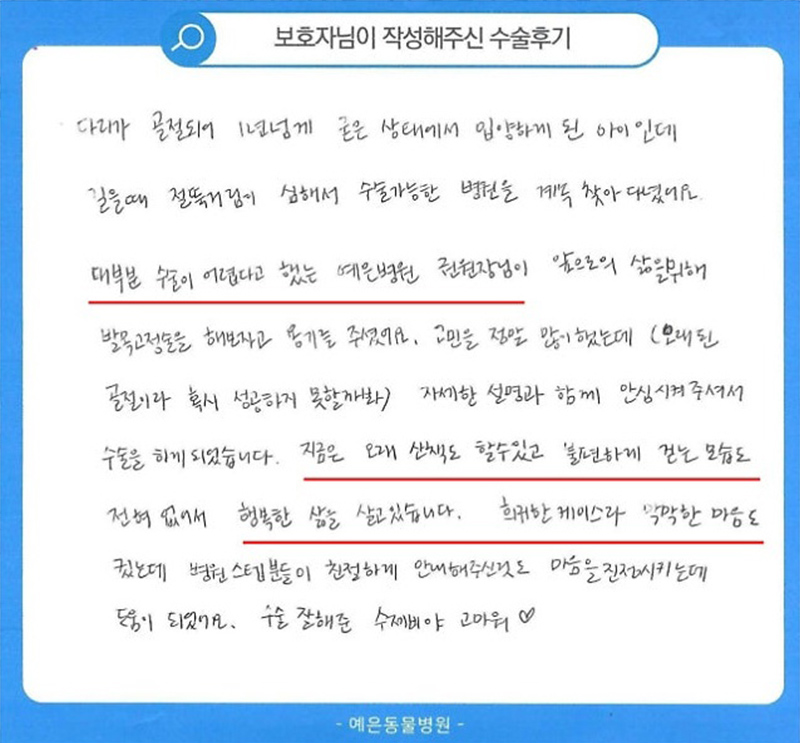

치료 후기

다리가 골절되어 1년 넘게 굳은 상태에서 입양하게 된 아이인데 걸을 때 절뚝거림이 심해서

수술 가능한 병원을 계속 찾아 다녔어요. 대부분 수술이 어렵다고 했는데

예은병원 권원장님이 앞으로의 삶을 위해 발목고정술을 해보자고 용기를 주셨어요.

고민을 정말 많이 했는데 (오래 된 골절이라 혹시 성공하지 못할까봐) 자세한 설명과 함께

안심시켜주셔서 수술을 하게 되었습니다. 지금은 오래 산책도 할 수 있고 불편하게 걷는 모습도

전혀 없어서 행복한 삶을 살고있습니다. 희귀한 케이스라 막막한 마음도 컸는데 병원 스텝분들이

친절하게 안내해주신 것도 마음을 진정시키는데 도움이 되었어요. 수술 잘해준 수제비야 고마워